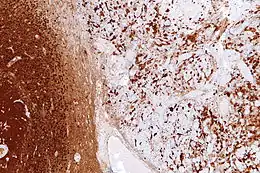

Image of gliosis in tissue

Micrograph showing gliosis in the cerebellum. Reactive astrocytes on the left display severe proliferation and domain overlap.